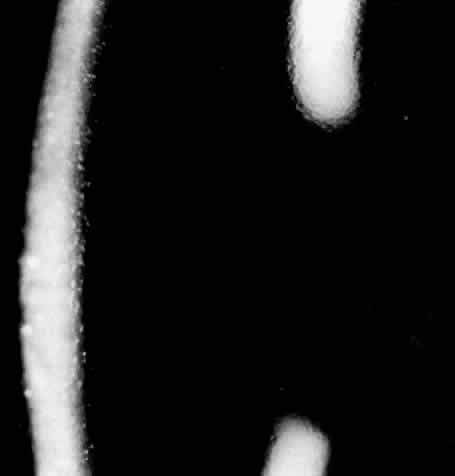

Slit lamp examination of young patients may only reveal small white or refractile anterior stromal spots in the central cornea. These spots often confused early investigators, leading some to misidentify this disorder as granular dystrophy. Later, the branching icicle-like lines (Fig. 7) appear in the anterior and then posterior stromal levels. The subepithelial location of many of these deposits lead to erosion of the overlying epithelium. Subepithelial scarring with destruction of Bowman's membrane then may take place allowing further opacification of the cornea and obscuration of the original lattice pattern. With further scarring, erosive episodes are less and corneal hypesthesia occurs.74 Other patients may have deeper stromal involvement, fewer epithelial erosions, and continued good vision until much later in life.

Fig. 7. Lattice dystrophy: typical branching filaments and similar irregular opacities.